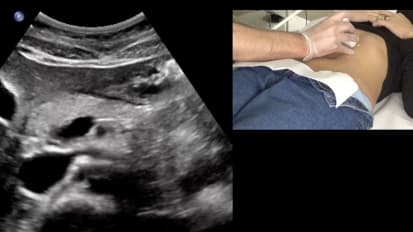

Duplex Ultrasound: Pelvic Reflux Video

Duplex Ultrasound: Pelvic Reflux

Featuring: Nicos Labropoulos, PhD, RVT, and Adriano Souza, MD; Duration: 25 minutes